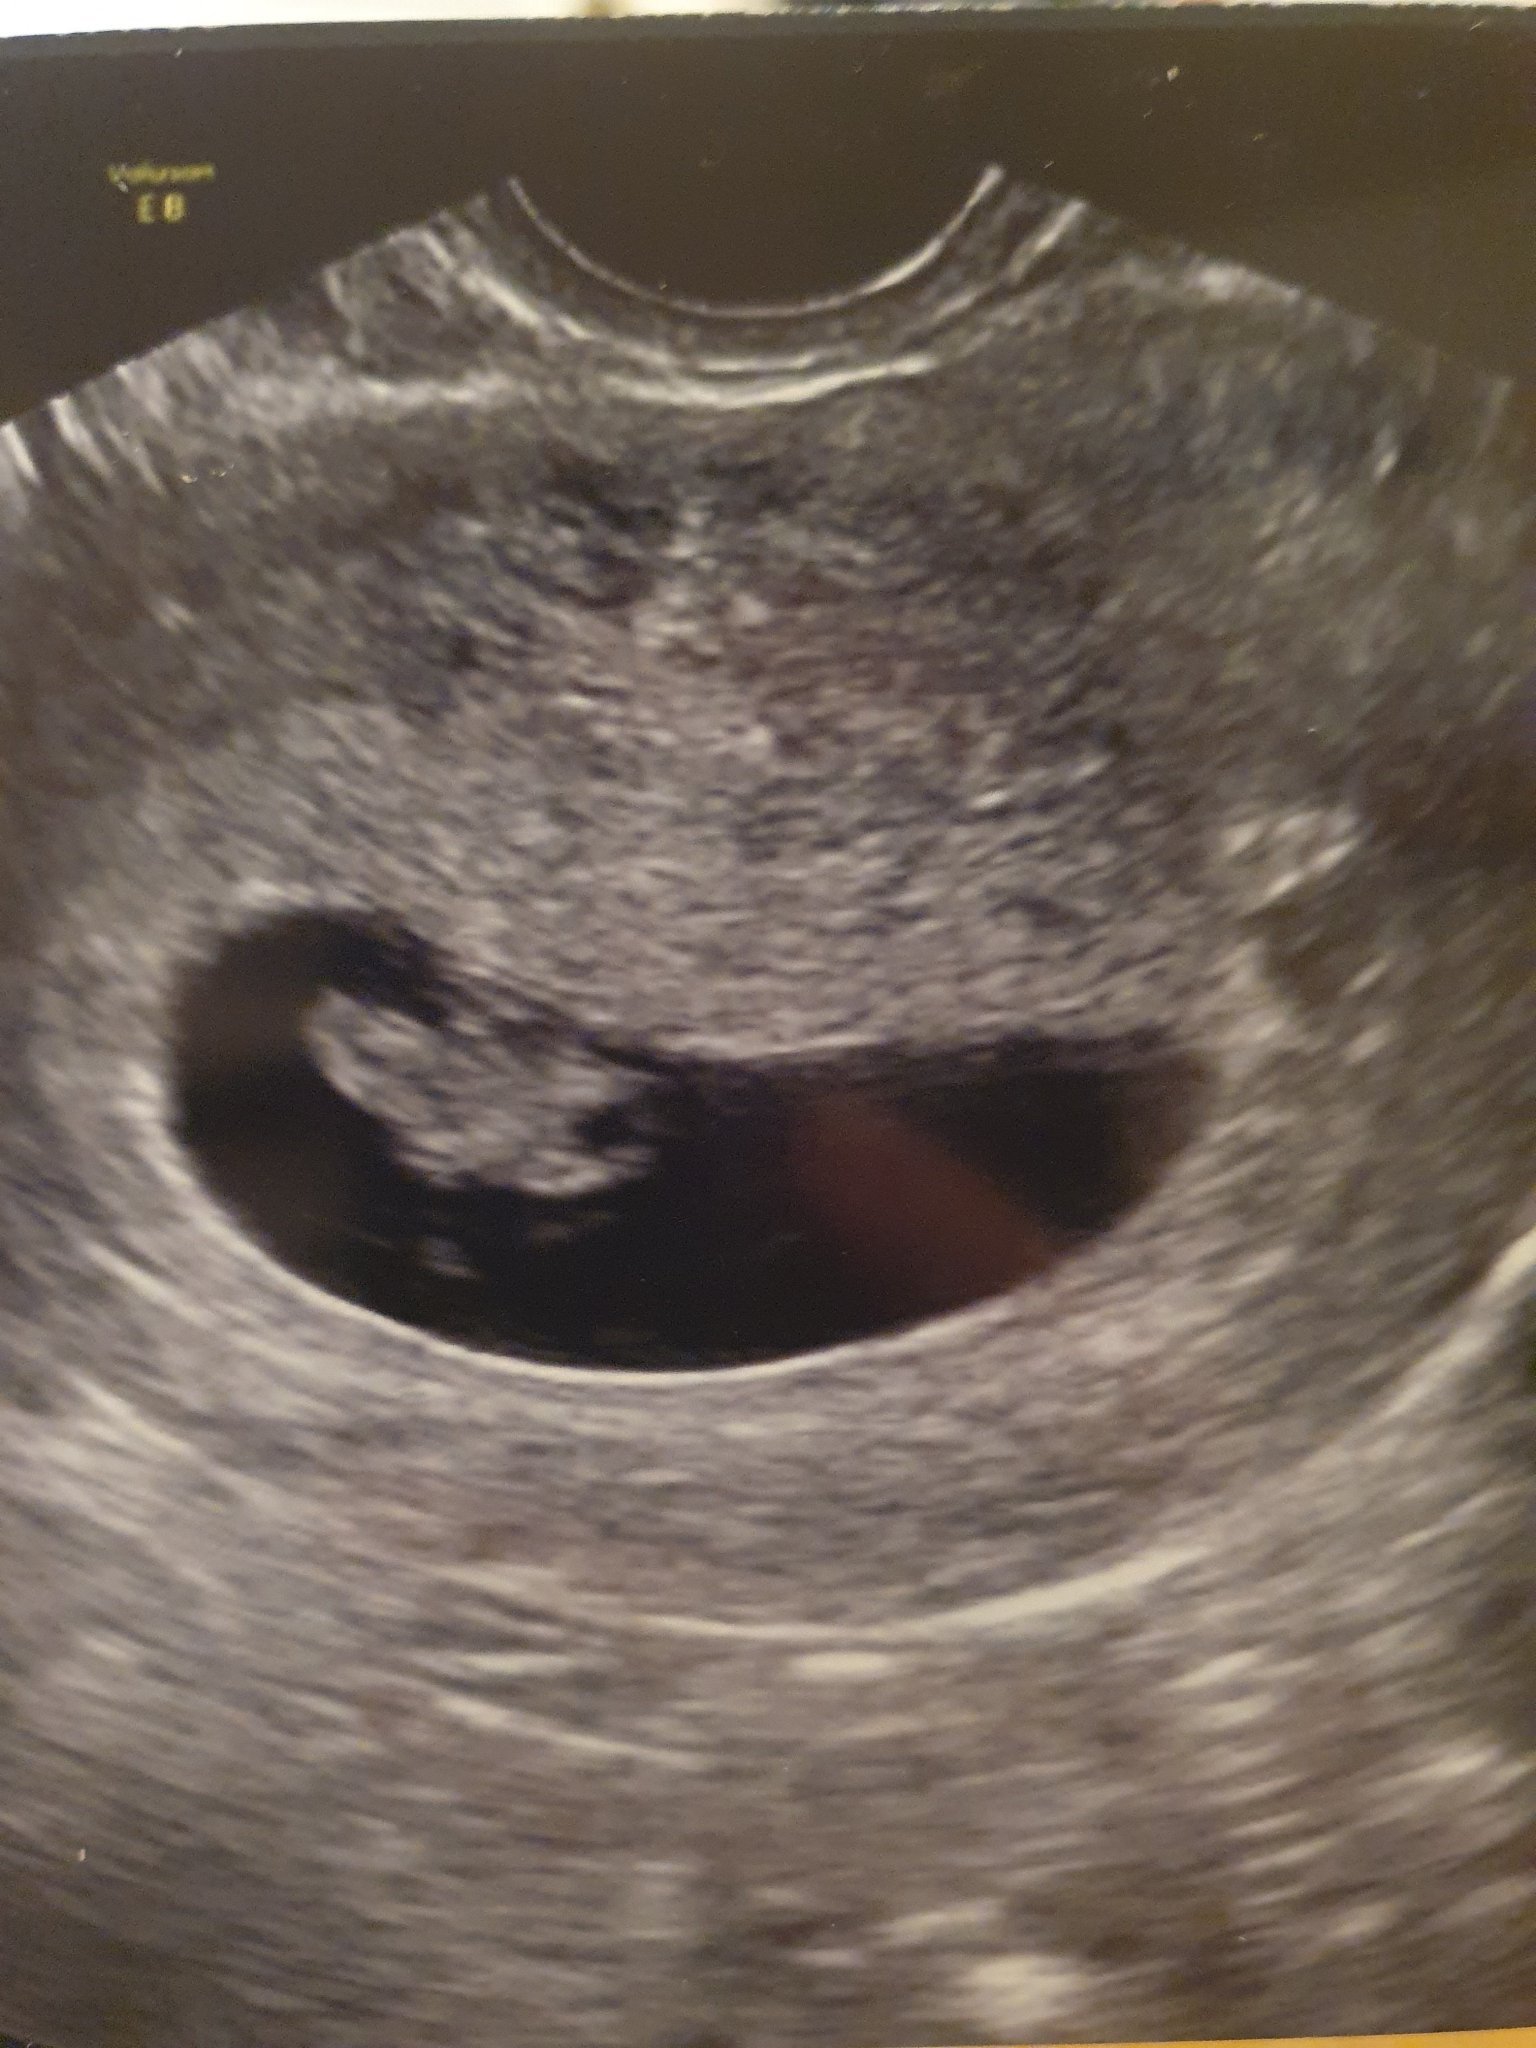

Какви са обичайните симптоми на бременността и как могат да бъдат управлявани?

Какви са процедурите за получаване на направление за прегледи по време на бременност?

Кога трябва да отида на преглед, за да се уверя, че всичко е наред?